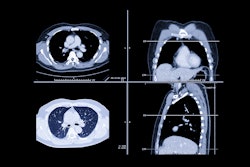

In the current study, the authors sought to explore the prevalence of emphysema on CT imaging among people with normal spirometry results and to determine if the rate differs between black and white individuals.

The group used data from the CARDIA (Coronary Artery Risk Development in Young Adults) study between 2015 to 2016, as well as information from CT scans performed between 2010 to 2011. The research included 2,674 participants, of which 485 were Black men, 762 Black women, 659 white men, and 768 white women; all participants had both a CT exam and spirometry available for analysis. Primary outcome was visual identification of emphysema on CT, not spirometry results.

The investigators tracked patients' self-identified race category and visually identified emphysema on CT exam across a range of spirometry results using a metric called race-specific forced expiratory volume in one second (FEV1) across different percentage ranges (between 80% and 99% and 100% and 120%). (FEV1 measures the amount of air a person can force out of their lungs in one second; a race-specific version is adjusted to lower values for Black individuals.)

Of the study participants with a race-specific FEV1 between 80% and 99% of predicted, 6.5% had emphysema, and the occurrence of the disease was higher among both Black men and women compared with their white counterparts. Of those with a race-specific FEV1 between 100% and 120% of predicted, 4% had emphysema, with Black men having a higher prevalence compared with white men and Black and white women having a similar rate.